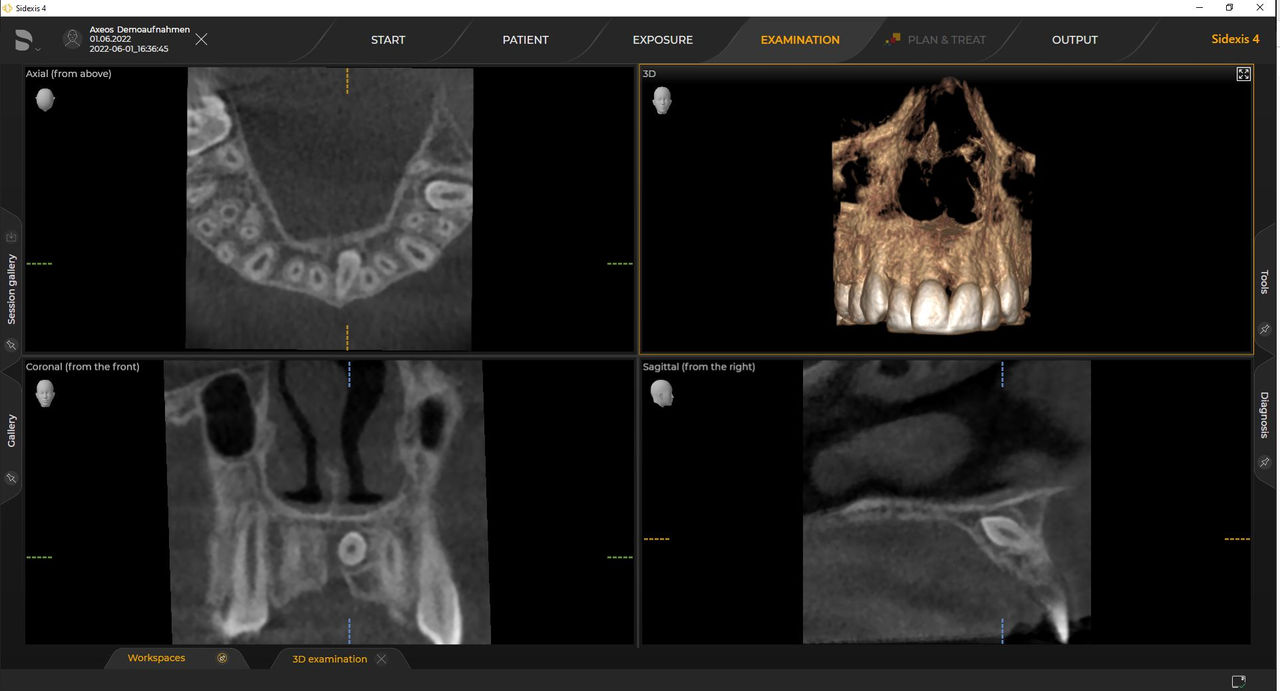

Numerous volume sizes ensure flexibility in everyday practice. Examine a precise area or evaluate the complete dentition including the TMJs

Dentsply Sirona 3D units work exclusively with Sidexis 4. Nevertheless data migration from Sidexis XG to Sidexis 4 is very easy. Sidexis 4 allows for the full digital experience with the latest tools.